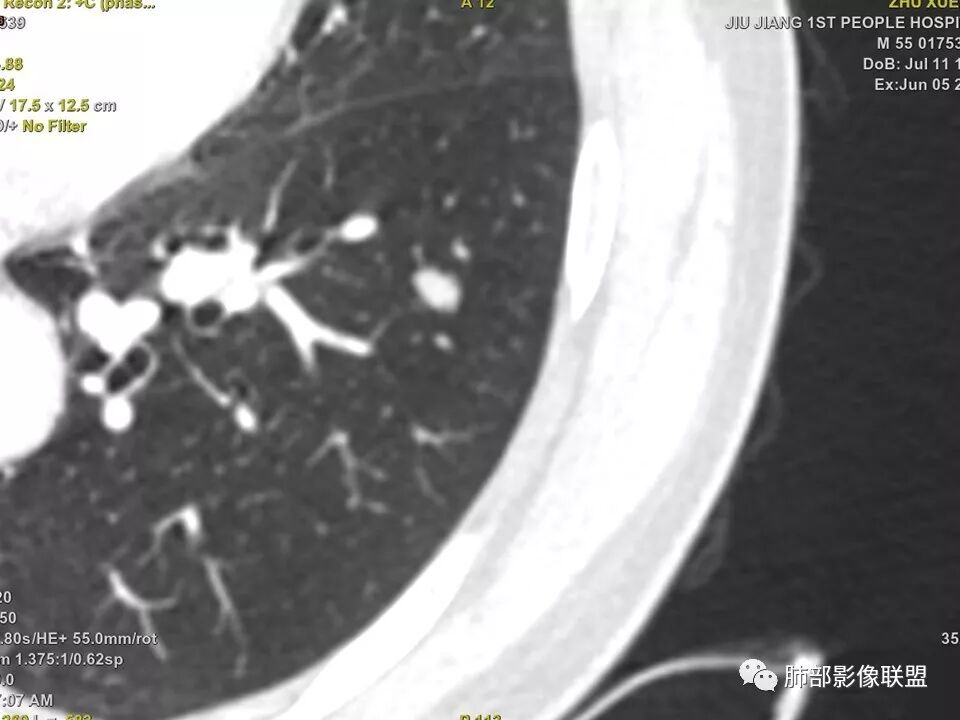

中年男性,左肺下叶不规则实性结节,有分叶及棘状凸起,支气管截断,轻度不均匀强化,考虑鳞癌,鉴别炎性肉芽肿。

实性结节,深分叶,支气管截断,考虑腺癌。只是强化有点低。鉴别:肉芽肿病变。

左肺下叶前内基底段结节 深分叶和脐凹 表面部分膨隆 部分收缩 支气管截断 轻度强化 中央有坏死 考虑鳞癌 鉴别炎性结节

中年男性,支气管门口截断、邻近支气管未见管壁增厚,分叶明显,边缘彭隆,内见小坏死灶,周围未见GGO,考虑周围性鳞癌,鉴别炎性肉芽肿。

病灶多结节融合,有分叶,也支气管截断,有细小血管连接,考虑恶性结节,周围型肺癌。

中年男性,左肺下叶不规则实性结节,有桑葚感和分叶,支气管截断,不均匀强化,有坏死,考虑鳞癌可能性大。

左下肺前内基底段结节灶,边缘分叶,相应支气管截断,增强后轻度强化,中央可见坏死。考虑麟癌。